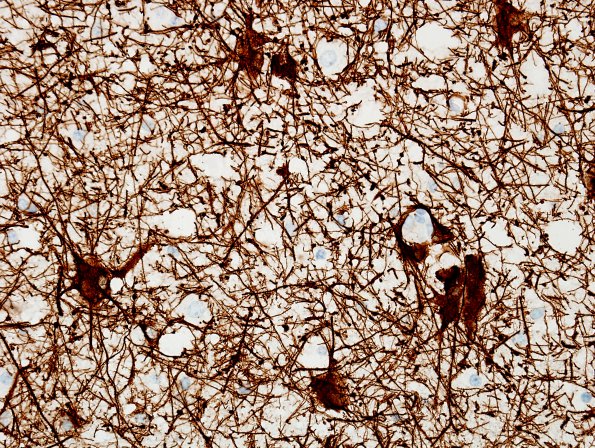

17C Ganglioglioma (Case 17) GFAP.jpg

The glial portion of the tumor is positive for glial fibrillary acidic protein (GFAP IHC).